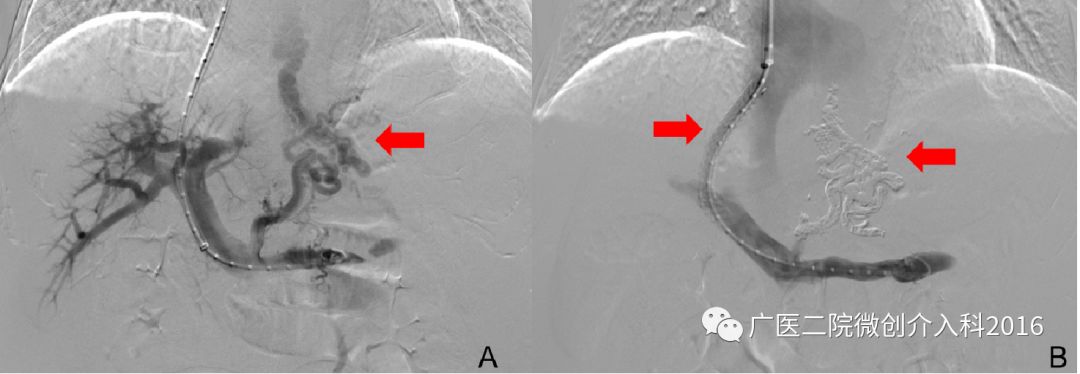

患者为肝硬化导致的食管胃底静脉曲张破裂出血,图A可见胃底粗大的曲张静脉。我们通过经颈静脉肝内门体分流术(TIPS)联合曲张静脉栓塞术(PTVE),一方面通过TIPS分流降低门静脉压力,另一方面通过PTVE栓塞出血的曲张静脉,共同达到减压、止血的目的。图B可见TIPS分流术后门静脉至肝静脉的分流通道,PTVE栓塞术后原曲张静脉消失。术后患者出血立即停止,生命体征逐渐平稳,止血效果立竿见影。